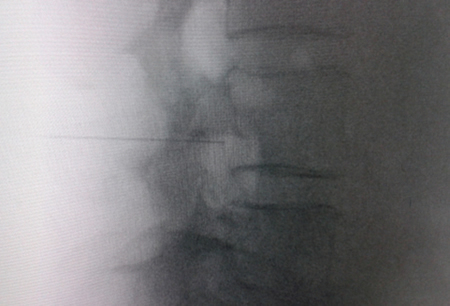

El acceso por vía transforaminal es el más utilizado (4). Se coloca al paciente en decúbito prono con una almohada a nivel abdominal para revertir la lordosis fisiológica. Las agujas o cánulas de radiofrecuencia que utilizamos con más frecuencia son de diámetro 20 o 22 G de 98 mm de largo con punta activa de 0,5 o 1 cm. Después de la asepsia con clorhexidina alcohólica y la colocación de campos estériles, se realizan enfoques radiológicos en incidencia anteroposterior, oblicuo y lateral. En incidencia anteroposterior y moviendo el arco en dirección cráneo caudal se borra el doble arco del borde inferior vertebral. En incidencia oblicua entre 20 y 30 grados ipsilateral al GRD a tratar, se visualizará la clásica imagen descrita como de “Scotty Dog”, que es resultado de acercar el macizo facetario y la apófisis espinosa al lado contralateral. El punto de entrada será entonces inmediatamente debajo del pedículo. Previa anestesia local con lidocaína al 1 %, la aguja se introducirá siguiendo una visión túnel y no se avanzará más allá de la mitad del pedículo en esta proyección con la finalidad de prevenir la lesión neural. En proyección lateral, se introducirá en el techo del neuroforamen

(Figuras 1 y 2) pero la localización final será determinada por la estimulación nerviosa sensitivo-motora. La estimulación sensitiva consiste en provocar parestesia o dolor en el territorio afectado con una estimulación entre 0,3-0,6 v. Durante la estimulación motora se pueden provocar fasciculaciones en el territorio afectado con un voltaje del doble al necesario para provocar las parestesias. Si se desea realizar una denervación intraganglionar, promulgada por algunos autores, la estimulación tanto sensorial como motora será positiva a menos de 0,3 v. Por tratarse de un procedimiento más doloroso, se aconseja administrar anestésicos locales después del estímulo doloroso y antes de realizar el tratamiento. La impedancia deberá mantenerse por debajo de 450 ohms, lo que se consigue infundiendo solución salina previa a la RF (4). La utilización de contraste constituye una buena práctica, ya que descarta la posición intravascular e intratecal de la cánula de radiofrecuencia.

Fig. 1. Vista radiológica de perfil que muestra una cánula de radiofrecuencia en el ángulo anterosuperior o techo del neuroforamen, topografía aproximada del ganglio de la raíz dorsal